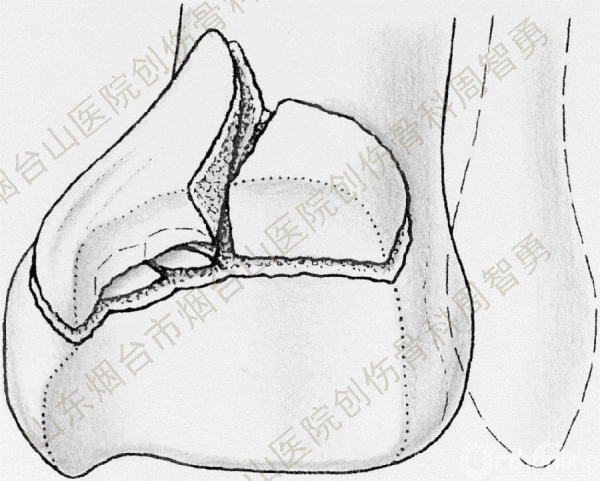

↑ 图 5ab

图 5 经踝关节后外侧入路显露后侧骨折块(a),分别以胫后肌腱腱鞘和下胫腓后韧带为铰链将后内侧骨折块和后外侧骨折块翻向内侧和外侧,显露并复位后内侧骨折块腹侧向近端塌陷的骨软骨骨折块(b)